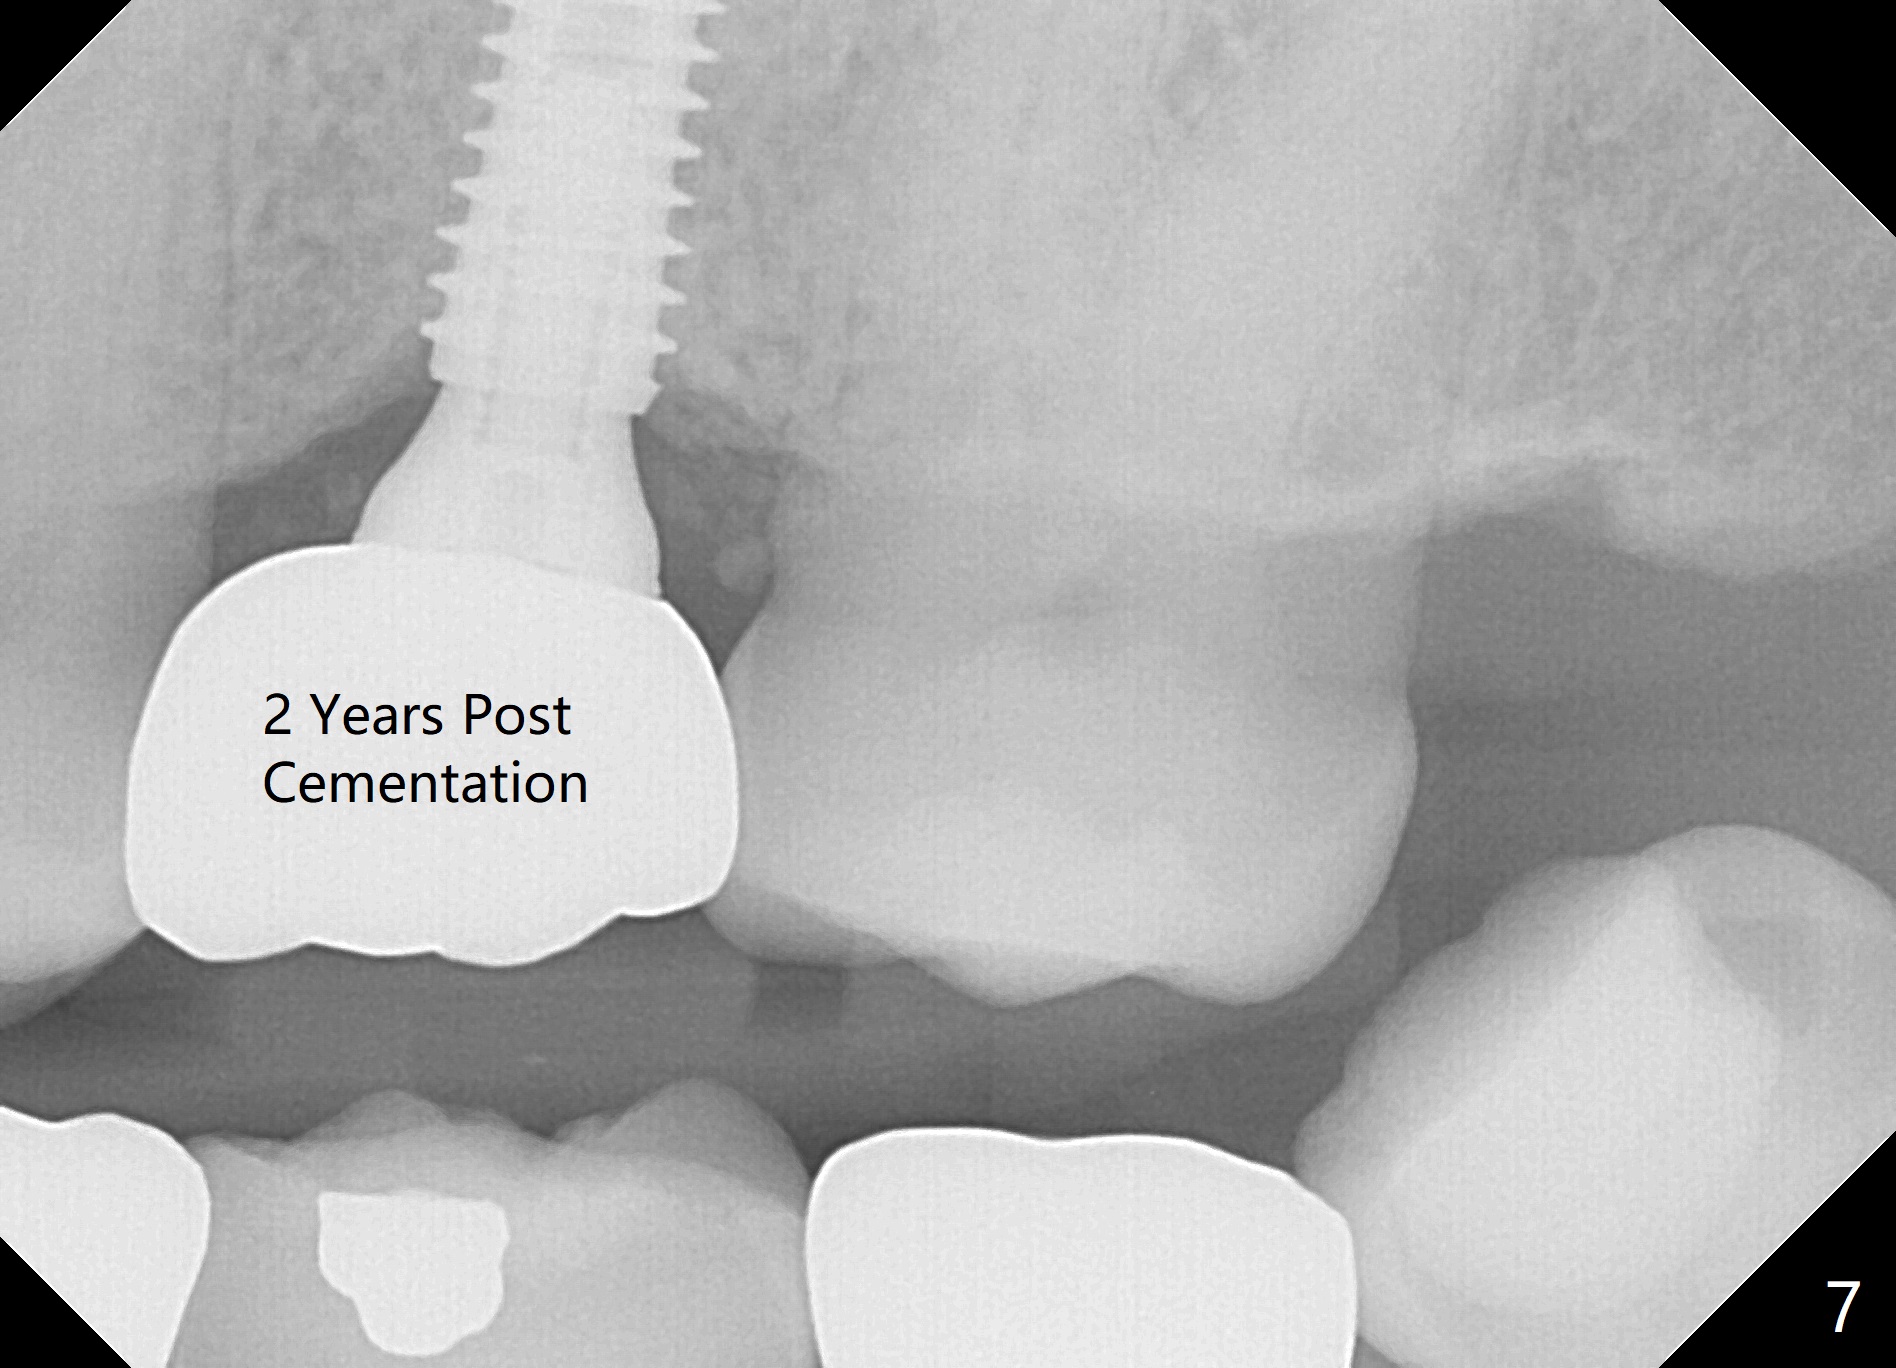

The edentulous area at #14 is moderately atrophic, After incision, the bone is too hard for #15 blade for bone expansion. Osteotomy is initiated with 1.2 mm drill, followed by insertion 1.3/2.3 mm bone expander (Fig.1). Use the same instruments are reused twice to change the trajectory (Fig.2,3). Finally Lindamann bur is utilized to move the osteotomy distally by ~ 2 mm; bone expansion continues until 2.4/3.7 mm expander for 13 mm with 50 Ncm (Fig.4). The last expander 3/4.4 mm barely enters the osteotomy for 6 mm. A 3.7 mm drill has to be used for 12 mm before placement of a 4.5x11.5 mm implant with >35 Ncm (Fig.5). A 5.5x5(3) mm abutment is placed with allograft (<) placed around the implant. Following suturing, periodontal dressing is applied around the implant. The abutment dislodges 3 months postop (Fig.6). Crown is delivered 3 weeks later. The abutment screw is retightened ~ 2 months later. He is a bruxer. The abutment screw is loose again <2 years post cementation (6 months post #18 screw retightenting and occlusal reduction), probably related to distal implant placement (Fig.7).